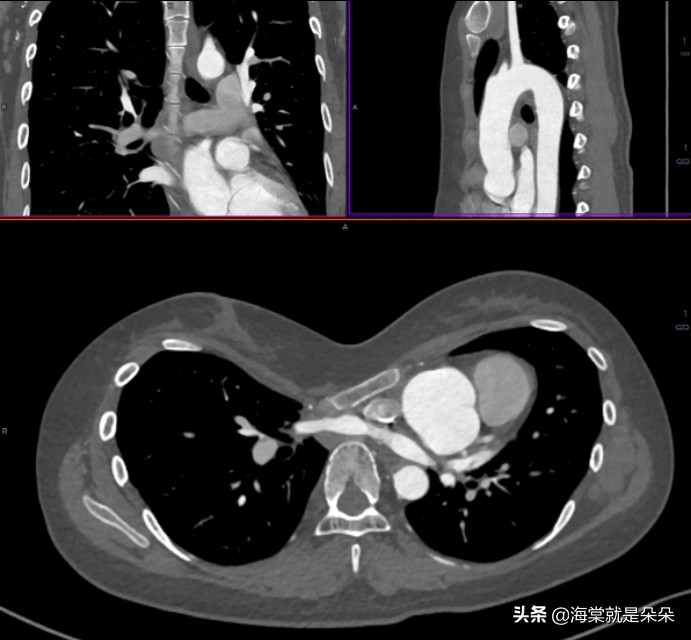

国际上评估漏斗胸的畸形指数,普遍使

用 Haller指数,关于漏斗最深点到脊柱前方距离、胸骨最凹陷处层面胸廓的最大横径。

正常人的 HI 平均指数是 2.52,漏斗胸患者则超过 3.2,大于 3.5 为重度漏斗胸,3.25 到 3.5 为中度,小于 3.25 为轻度。

这个女孩20岁才来就诊,Haller指数达到了16!胸骨体都快贴到胸椎了!心脏大血管受压迫移到左边,主动脉窦膨大!

她是体检超声怀疑主动脉瘤的,吓哭了。但是这个漏斗胸确实已经发展到影响器官发育和功能了。需要做手术。